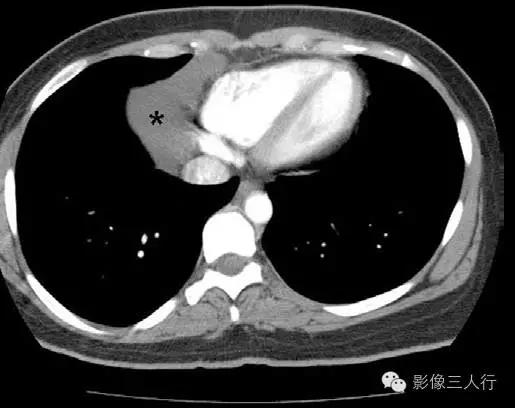

图1:胸部CT平扫显示液体密度肿块(*)起于纵隔右侧。未见壁存在,肿块与心包相连。表现为典型心包囊肿